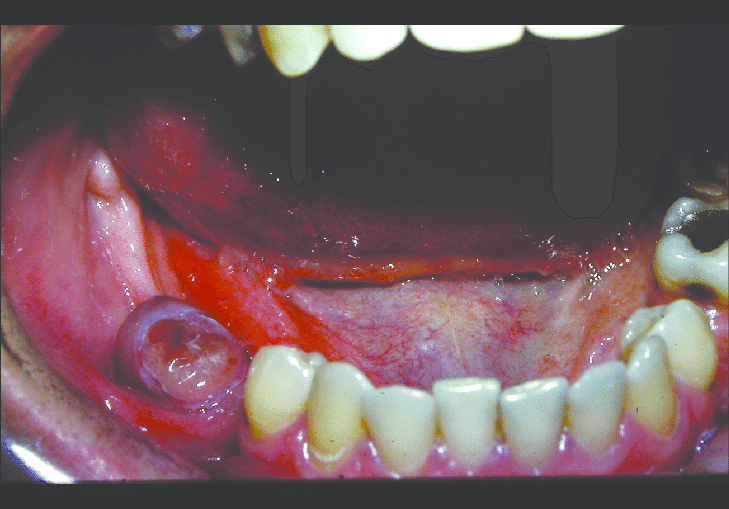

A 58-year-old man presented with a brown–red granular epulis. A periapical radiograph showed underlying bone destruction and a biopsy was reported as showing osteoclast-like giant cells in a spindle-cell background with numerous thin- walled vessels. Haemosiderin and extravasated red cells were abundant.

The clinical and radiographic findings suggest that the 58-year-old man may have a peripheral giant-cell granuloma (PGCG). This is a benign, non-cancerous tumor that often arises from the gum tissue and can cause bone destruction in the underlying jawbone.

The biopsy findings support the diagnosis of PGCG, as the presence of osteoclast-like giant cells and spindle cells in a background of abundant thin-walled vessels is characteristic of this condition. The haemosiderin and extravasated red cells seen in the biopsy are likely a result of bleeding within the lesion, which is common in PGCG.